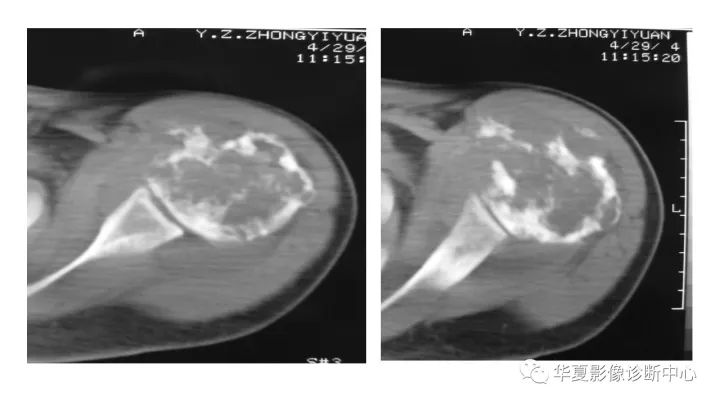

肱骨上段软骨肉瘤1例X线CT及MR影像表现

【病例】肱骨上段软骨肉瘤1例X线CT及MR影像表现